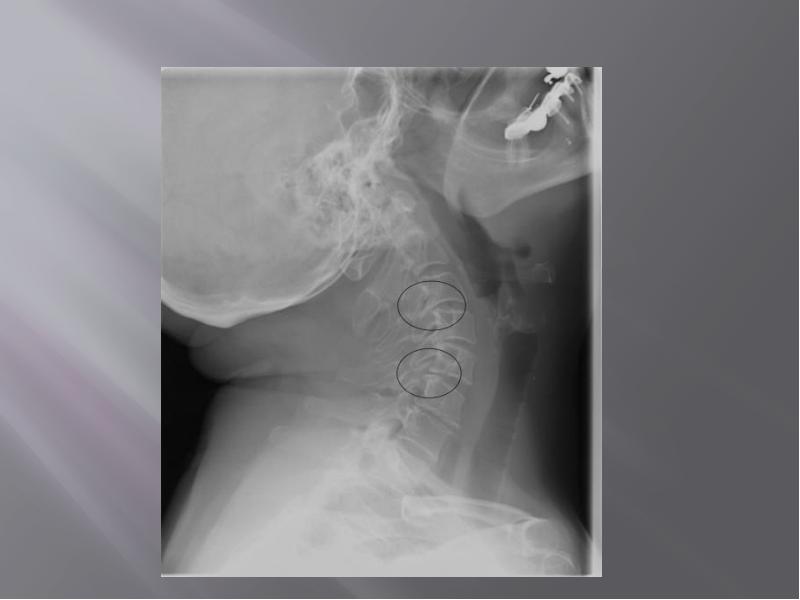

- 43. Рентгенография позвоночника при остеохондрозе позволяет выявить изменения позвоночника, такие как: Рентгенография

- 44. Обзорная рентгенография в 2-х стандартных проекциях (боковая и задняя) позволяет оценить